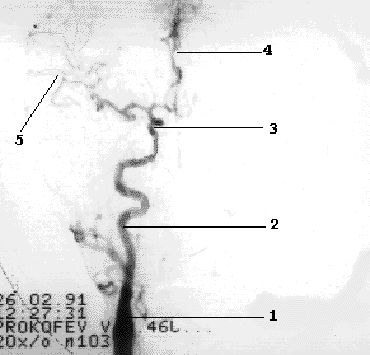

Рис 1.5 Интракраниальные ветви ВСА. 1- ОСА, 2- ВСА, 3- сифон ВСА, 4- ПМА, 5- СМА.